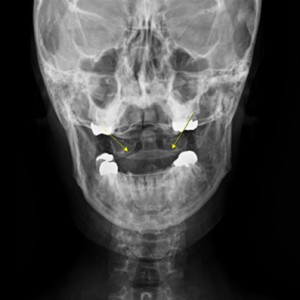

안면 두개골 엑스레이 검사

Submento Vertex View 포함

안면 두개골 CT

경추 1,2번의 변위 파악